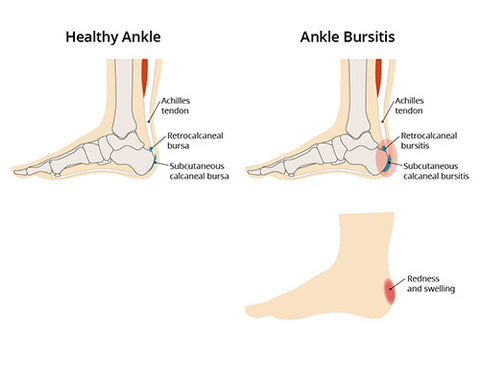

Product Item: Swollen achilles tendon treatment dealsAchilles tendon injuries healthdirect deals, Achilles Tendinitis Symptoms Treatment deals, How to Relieve Achilles Tendonitis in SECONDS deals, Achilles Tendinitis OrthoInfo AAOS deals, Achilles Tendinitis Exercises to Heal and Strengthen Your Tendon deals, Achilles Tendon Pain Causes Treatments Prevention deals, Achilles tendon Overview Mayo Clinic Orthopedics Sports Medicine deals, Achilles Tendonitis Symptoms and Treatment Caruso Foot and Ankle deals, Tendinopathy Symptoms Causes Treatment deals, Achilles Tendinitis OrthoInfo AAOS deals, Chronic Achilles Tendon Pain Diagnosis Treatment HSS deals, Know the Symptoms of Achilles Tendonitis Tendinopathy Gait Happens deals, Achilles tendinopathy Symptoms causes and treatment Bupa UK deals, Achilles Tendon Injuries deals, Swollen Achilles tendon Why does it swell and when can I exercise deals, Heal Your Achilles Tendonitis At Home Achilles Tendon Treatment deals, Achilles Tendonitis FootEducation deals, Achilles Tendinopathy Symptoms Treatments Recovery deals, Achilles Tendinopathy Causes Symptoms Treatment The Feet People Podiatry deals, How to fix Insertional Achilles Tendonitis deals, Achilles tendinitis Symptoms causes Mayo Clinic deals, Back of Achilles Tendon Heel Pain Shoes Orthotics Home Treatment deals, Achilles Tendonitis Causes Symptoms Signs Gleneagles Hospital deals, Achilles Tendinopathy NHS Lanarkshire deals, Achilles Tendinitis in Children Causes and Treatment deals, Achilles Tendonitis Common Symptoms Diagnosis and Treatment deals, Achilles Tendinitis Types Symptoms Causes Diagnosis Treatment and More deals, Achilles Tendinitis River Forest Rheumatoid Arthritis Elmhurst deals, Achilles tendinopathy is when you have micro tears in the tendon deals, Achilles swelling sales pain deals, Achilles Tendon Burning Pain Treatment Achilles Tendonitis deals, Achilles Tendinopathy Causes Symptoms Treatment The Feet People Podiatry deals, Exercises for Achilles pain Three gentle moves to get your rehab going deals, Achilles Tendinosis Treatment Symptoms and More deals, Achilles deals tendon swelling deals.